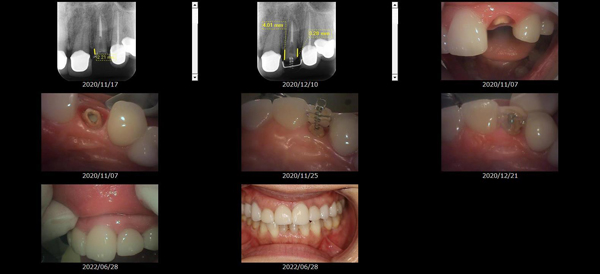

救歯MTM

虫歯が大きくて残せない歯、転倒などの事故により歯が根の深いとこで折れてしまったなどで、抜かざるを得ない歯を、骨の中に埋まっている健全な根を、骨の上に矯正的に引き上げることで、その歯を抜かず温存、救歯できる可能性のある治療方法です。

①健全な歯を、歯肉から見える位置にまで引き上げることで

根の治療の成功率を上げることが出来る。唾液には沢山の細菌がいます。唾液が入らない環境での根の治療を(神経の治療)を行うことで神経の治療、根の治療の成功率は格段と上がります。

②骨の上にある歯と土台で支える被せもの製作できる。

被せものを土台だけに頼ることなく、引き上げた健全な歯でも支えることで、歯への被せ物がしっかりと装着できるようになる。

③抜かずに歯を活かすことで、隣の歯を削るブリッジやインプラントにしないで済むことがある。

歯を矯正的に引き上げることで、その歯を救歯できるだけでなく、隣の歯を削るなどの侵襲を回避できる場合がある。

症例